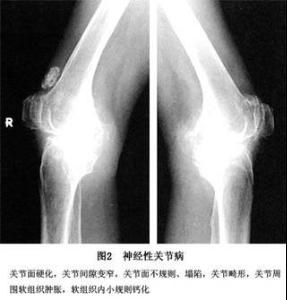

神經源性損害通常是肌電圖(誘發電位)檢測出來的,主要能影響到周圍神經(皮膚,肌肉,骨骼等)和神經末梢.前期主要表現為關節部位疼痛,一般呈對稱發生,兩邊交替並不同時疼痛,交換速度很快,每次疼的時間不會很長。通常帶有皮膚症狀,如:皮膚有燒灼感,在關節部位還會有很小的紅疹子,涼風刺激好發皮膚內部出現一塊塊的紫紅色。對環境嘈雜悶熱的地方十分敏感,很容易觸發,不要久,經常活動活動。